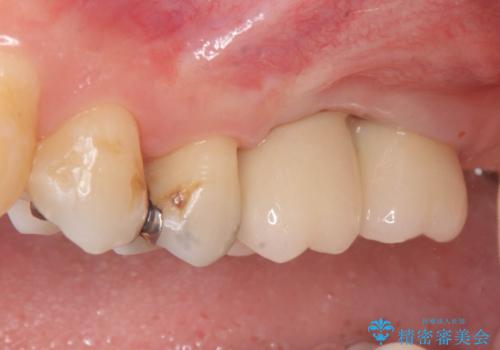

上顎奥歯のインプラント治療

- 88万円(インプラント×2・チタンカスタムアバットメント×2・ジルコニアクラウン×2・仮歯×2)費用は治療当時の料金となります

しっかりと食事ができるようになり、当院のインプラント治療に満足いただくことができました。